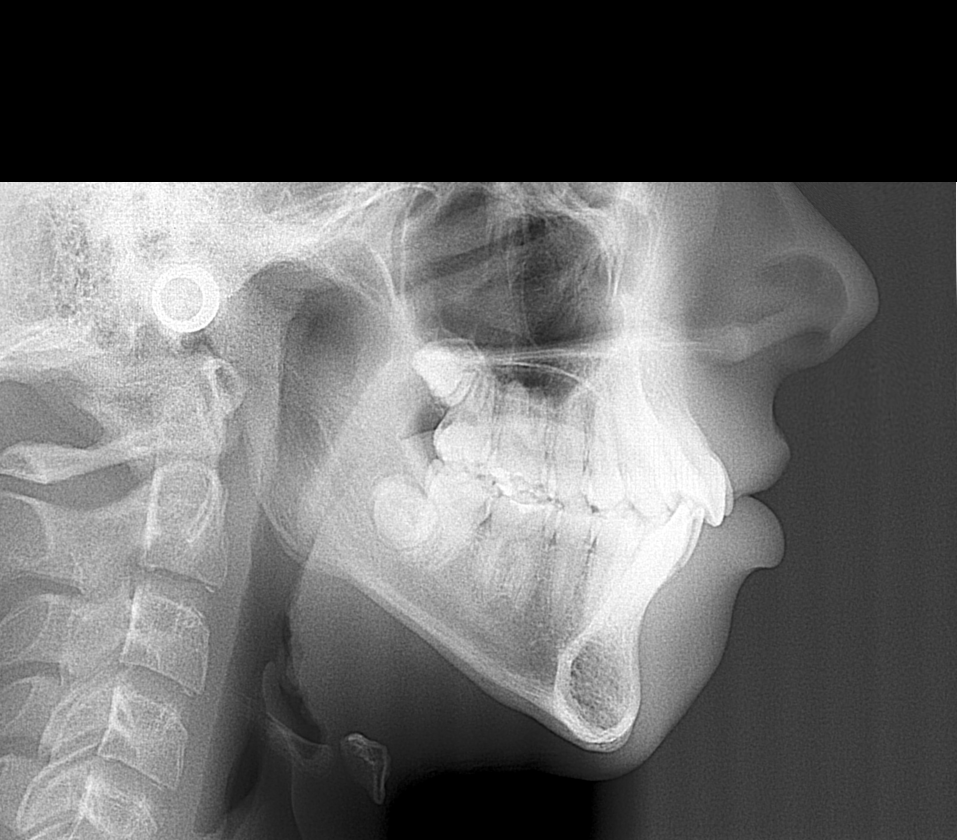

- You get at least an Xray scan so you can see what your jaw structure looks like

Example of such genioplasty in the case of a downgrown jaw

Dr John McHugh

- You get at least an Xray scan so you can see what your jaw structure looks like

Example of such genioplasty in the case of a downgrown jaw

Dr John McHugh